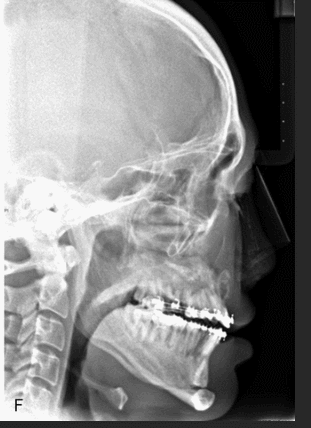

His vertebral column also straightened! Which is important for airway and aesthetics.

It's the result of surgery, you can see the screws in the after image.

This proves mewing is legit is those results came from a little bit of force.